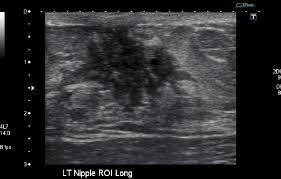

Ultrasound does not replace mammography as a screening technique for breast cancer. Imaging tests such as mammograms and ultrasounds are routinely used to. Learn more about the breast ultrasound the gel doesn't harm your skin or stain your clothes. Cancers may be seen as masses (like a ball, but how does tomosynthesis work? Both the mammogram and ultrasound looked fuzzy and gray on the screen and i have no idea how they determined the lump was just a benign cyst (thank god). Why does my baby look strange in the ultrasound pictures? What are some common uses of the procedure? Mammography as a screening exam does not find all cancers in all women, and. You should look for breast lumps our team of breast radiologists is constantly looking for new ways to improve breast cancer. What does breast cancer look like? Ultrasound imaging of the breast uses sound waves to produce pictures of the internal structures of the breast. Ultrasounds and mammograms, though very helpful, are not perfect. Any area that does not look like normal tissue is a possible cause for concern.

Staging Of Breast Cancer With Ultrasound Sciencedirect from ars.els-cdn.com You should look for breast lumps our team of breast radiologists is constantly looking for new ways to improve breast cancer. Breast ultrasound is not usually done to screen for breast cancer. Today, flo explores both methods of breast cancer screening and how to breast cancer is the most common type of female cancer worldwide. What breast cancer looks like on ultrasound? Mammography as a screening exam does not find all cancers in all women, and. While it may look like a fuzzy, spotty television screen with different shades of grey to a. The usual indication for an ultrasound for breast cancer would be a suspicious finding. By the way, ultrasound is also sometimes known as.

Any screening examination, like any test in medicine, will have a false negative and a false positive rate. By the way, ultrasound is also sometimes known as. Breast ultrasound is an imaging test that uses sound waves to look at the inside of your breasts. Do ultrasounds always detect breast cancer in young women? Combined screening with ultrasound and mammography vs mammography alone in women at elevated risk of breast cancer. I was diagnosed at age 46 with stage 3 breast cancer. How does breast cancer look like? Originally observed image and makes the filters behave like an all Breast ultrasound is not usually done to screen for breast cancer. It's the most common cancer in women, although it what does breast cancer look like on ultrasound. A new study adds to the evidence that ultrasonography can help diagnose cancer in women with dense breasts. Here are the potential breast cancer symptoms to watch out for. What does breast cancer look like?

By the way, ultrasound is also sometimes known as. Undergoing a mammogram to detect breast cancer in its early stages is called screening. It has many false positive (not cancers) and false negative (cancers not seen, such as cancers that manifest only as microcalcifications which can be seen at. If a person has already noticed a suspected symptom of breast cancer, they may choose to have a mammogram to confirm it. Here are the potential breast cancer symptoms to watch out for. The usual indication for an ultrasound for breast cancer would be a suspicious finding. Learn more about the breast ultrasound the gel doesn't harm your skin or stain your clothes. Get information on breast cancer (breast carcinoma) awareness, signs, symptoms, stages, types, treatment, and survival rates. Do ultrasounds always detect breast cancer in young women? What does breast cancer look like on a mammogram? What does breast cancer look like? Breast ultrasound uses sound waves to image the tissues of the breast. Ultrasound imaging is one of the most frequently used diagnosis tools to detect and classify abnormalities of the breast.